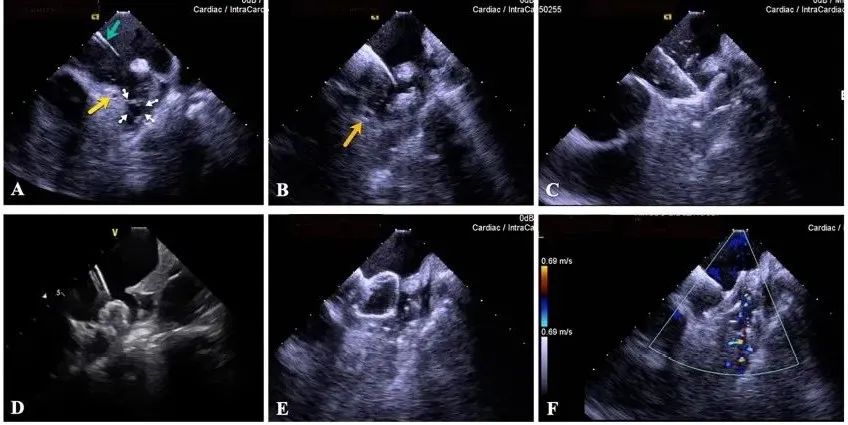

一種與心導(dǎo)管檢查相結(jié)合的超聲心動(dòng)圖診斷新興技術(shù),通過(guò)將超聲探頭置于心腔內(nèi)部,發(fā)射并接收超聲信號(hào),來(lái)精確獲取心臟解剖結(jié)構(gòu)、心臟血流動(dòng)力學(xué)等信息的實(shí)時(shí)成像。與其他影像技術(shù)相比,ICE技術(shù)具有操作簡(jiǎn)單、無(wú)輻射、安全性高、手術(shù)效率高、實(shí)用等優(yōu)勢(shì),ICE在很大程度上有望取代經(jīng)食道超聲心動(dòng)圖(TEE),成為電生理和結(jié)構(gòu)性心臟病領(lǐng)域的理想成像方式。

目前ICE技術(shù)已被應(yīng)用于左心耳封堵、房顫射頻消融、二尖瓣成形、房間隔缺損封堵等多種心臟介入手術(shù),應(yīng)用場(chǎng)景主要圍繞臟電生理、結(jié)構(gòu)性心臟病等領(lǐng)域,目前以電生理應(yīng)用為主。數(shù)據(jù)顯示,我國(guó)結(jié)構(gòu)性心臟病介入器械市場(chǎng)規(guī)模已從2017年的4億元增長(zhǎng)至2021年的20億元,年復(fù)合增長(zhǎng)率達(dá)48.3%;預(yù)計(jì)到2025年,該市場(chǎng)規(guī)模將達(dá)到104億元,可以預(yù)見(jiàn)ICE市場(chǎng)規(guī)模也將同步高速增長(zhǎng),未來(lái)市場(chǎng)發(fā)展空間廣闊。